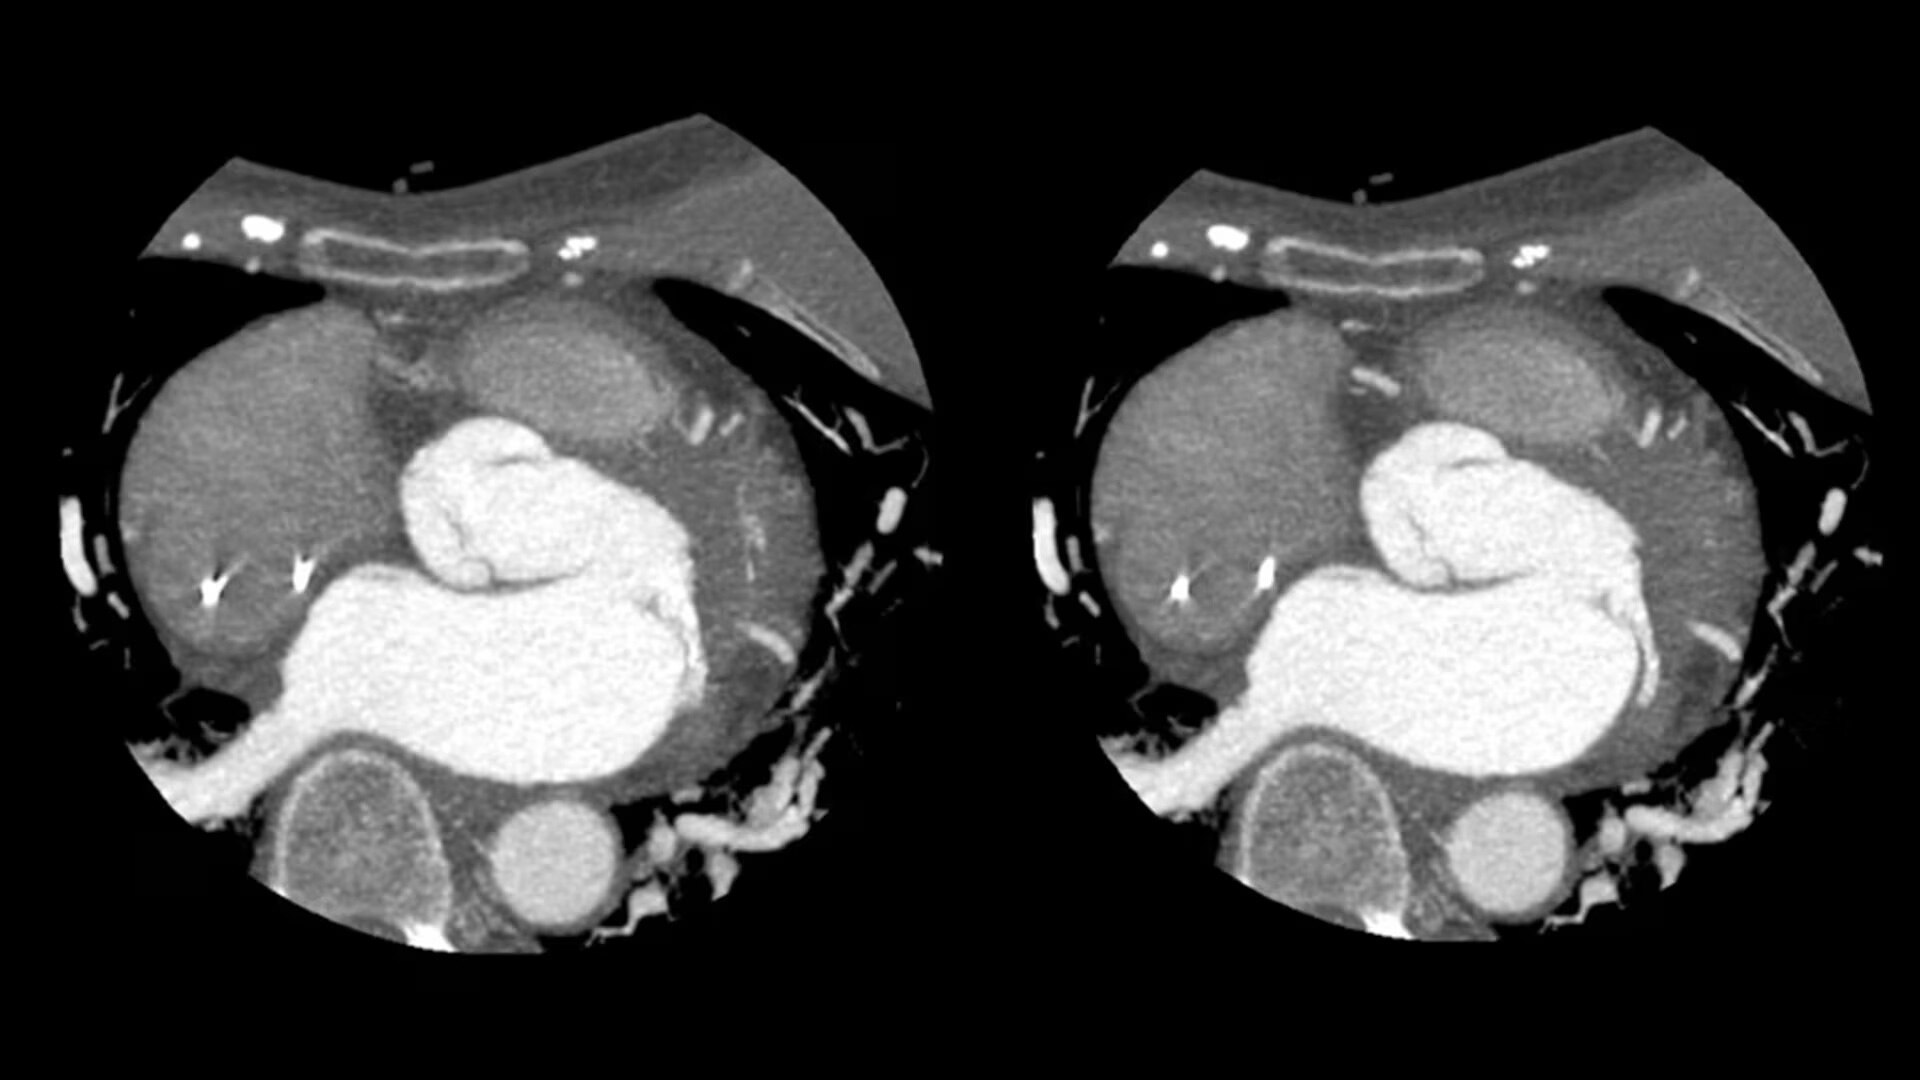

SnapShot Freeze 2

Intelligent and automated whole-heart motion correction for enhanced Cardiac CT imaging.

6x reduction in motion artifacts1

19.5 msec effective temporal resolution at 0.23s/rotation gantry speed2

Whole-heart motion correction